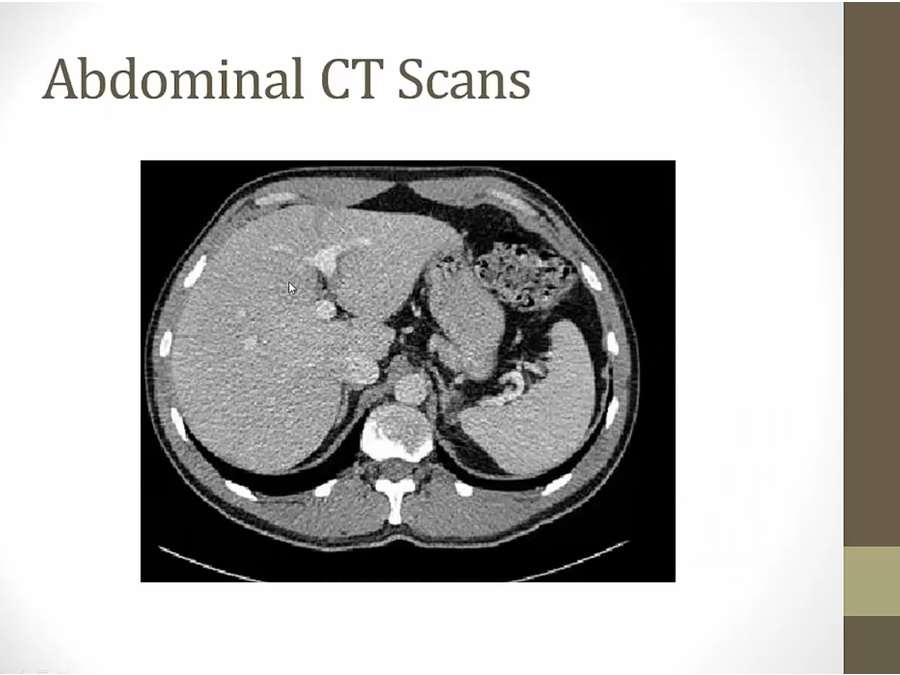

left:

liver: fairly high up, in axial

grey into liver: portal vein

left of liver: stomach with air inside